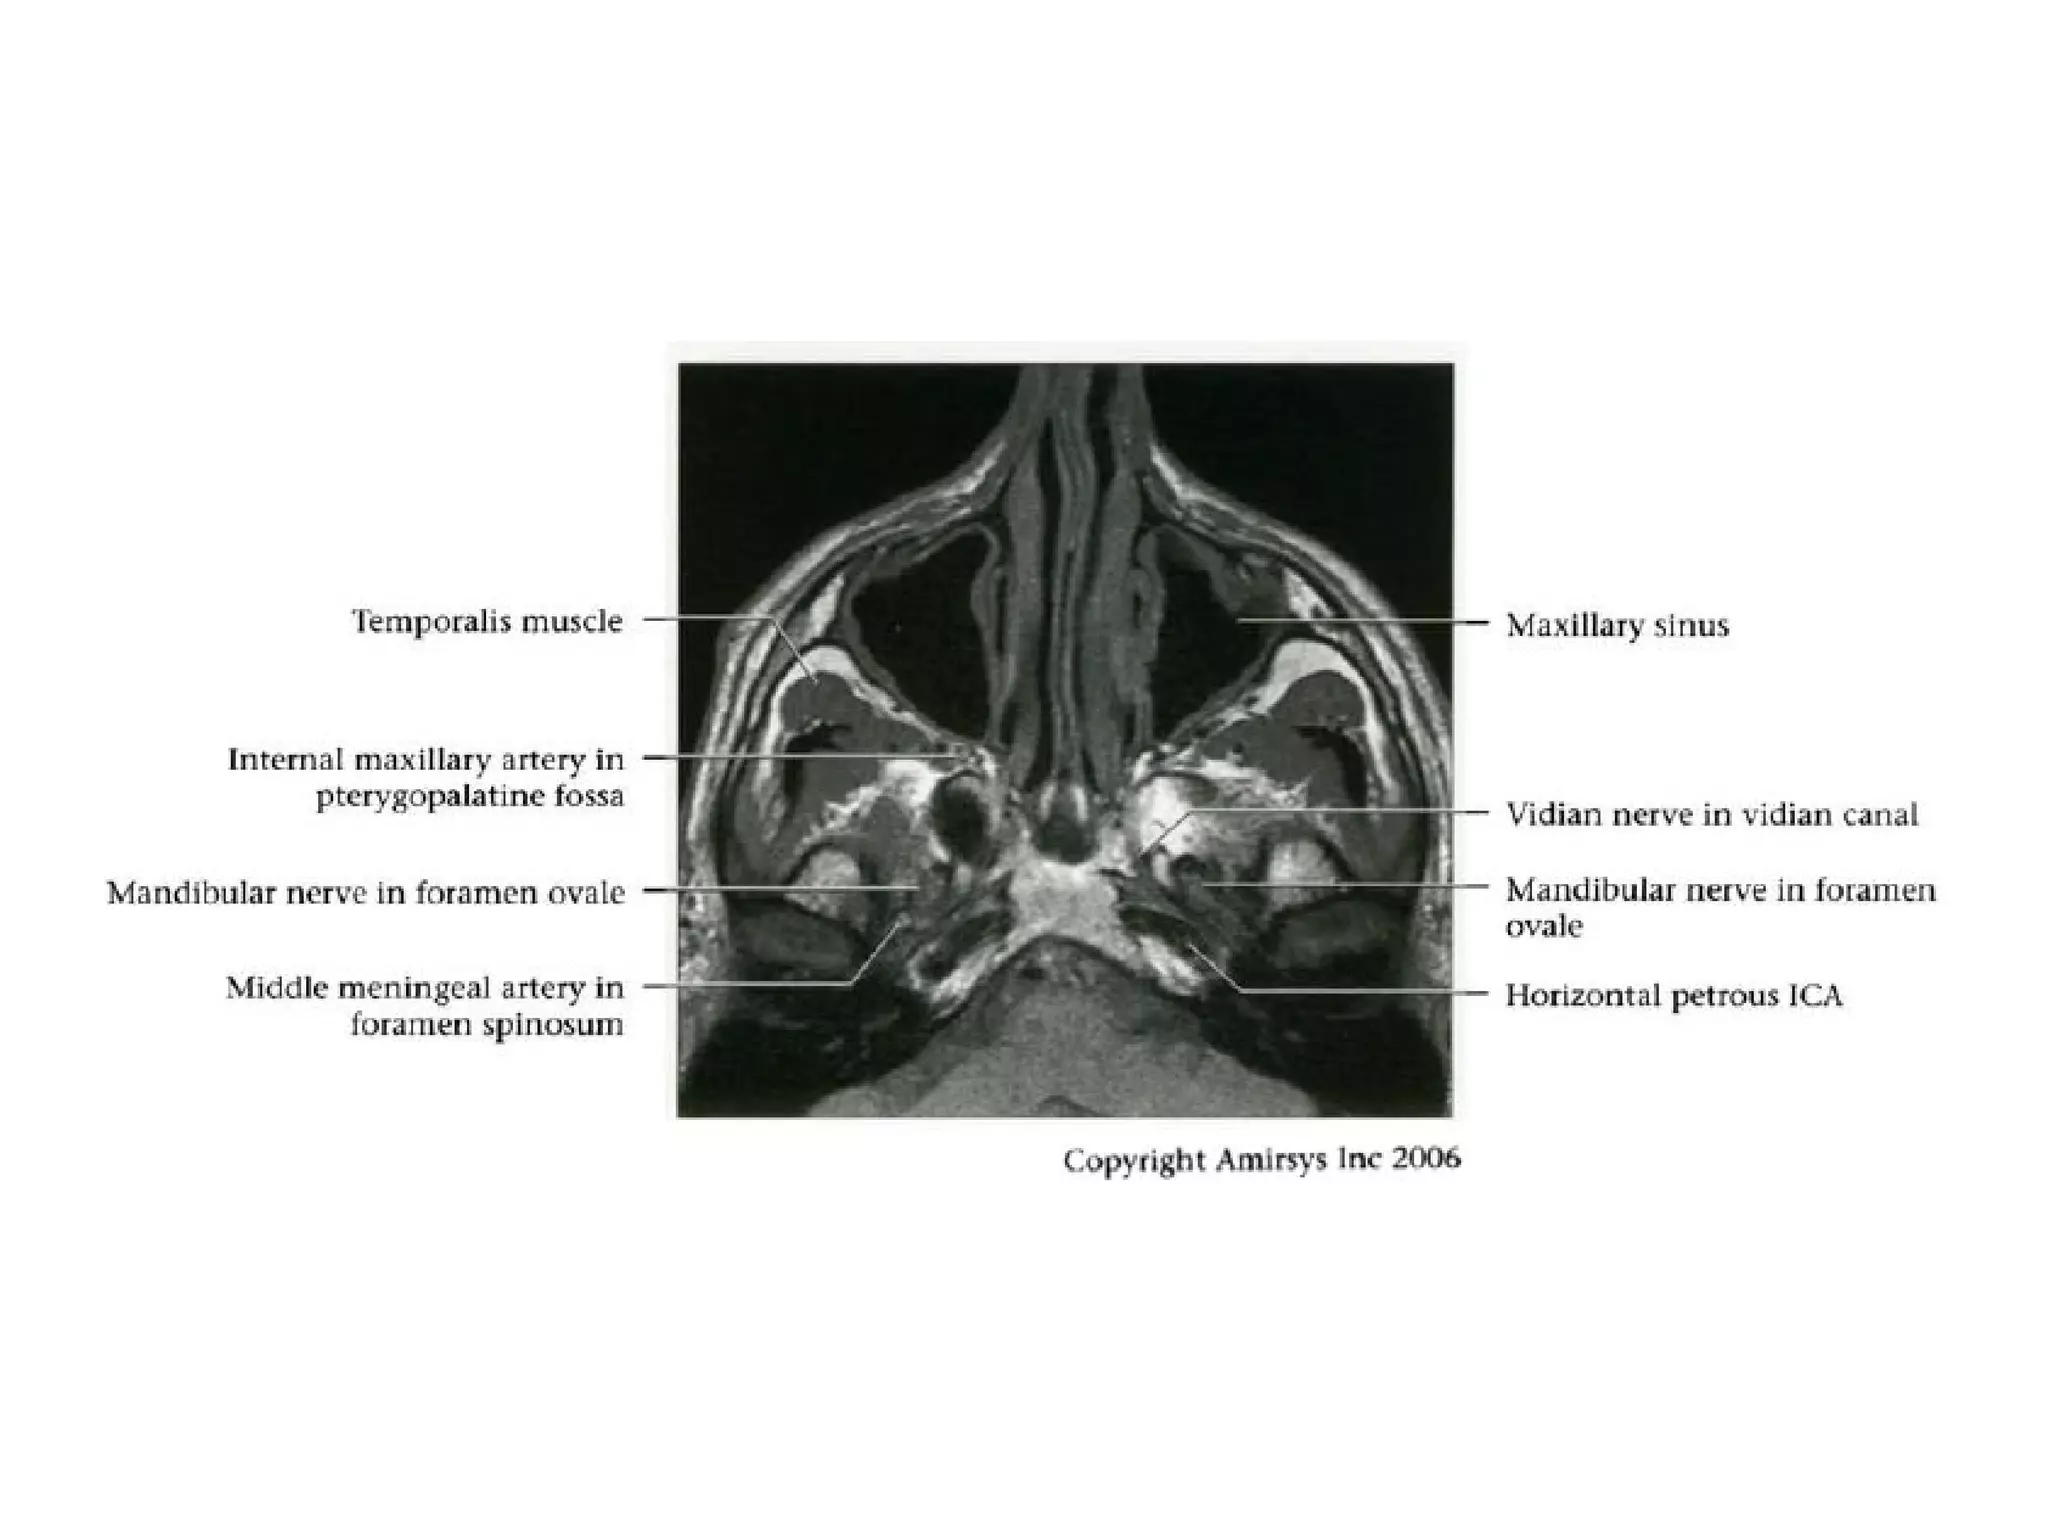

Divisions (Post-Ganglionic) of CNS

Mandibular nerve (CNV3)

• Does not pass through cavernous sinus

• Exits directly from Meckel cave, passing inferiorly

through foramen ovaIe into masticator space

• Carries both motor and sensory fibers

- Motor root bypasses TG, joins V3 as it exits through

foramen ovale

- Divides into masticator (muscles of mastication) and

mylohyoid nerves (mylohyoid and anterior belly of

digastric muscles)

- Masticator nerve take off just below skull base

- Mylohyoid nerve take off at mandibular foramen

• Main sensory branches include inferior alveolar, lingual

and auriculotemporal nerves